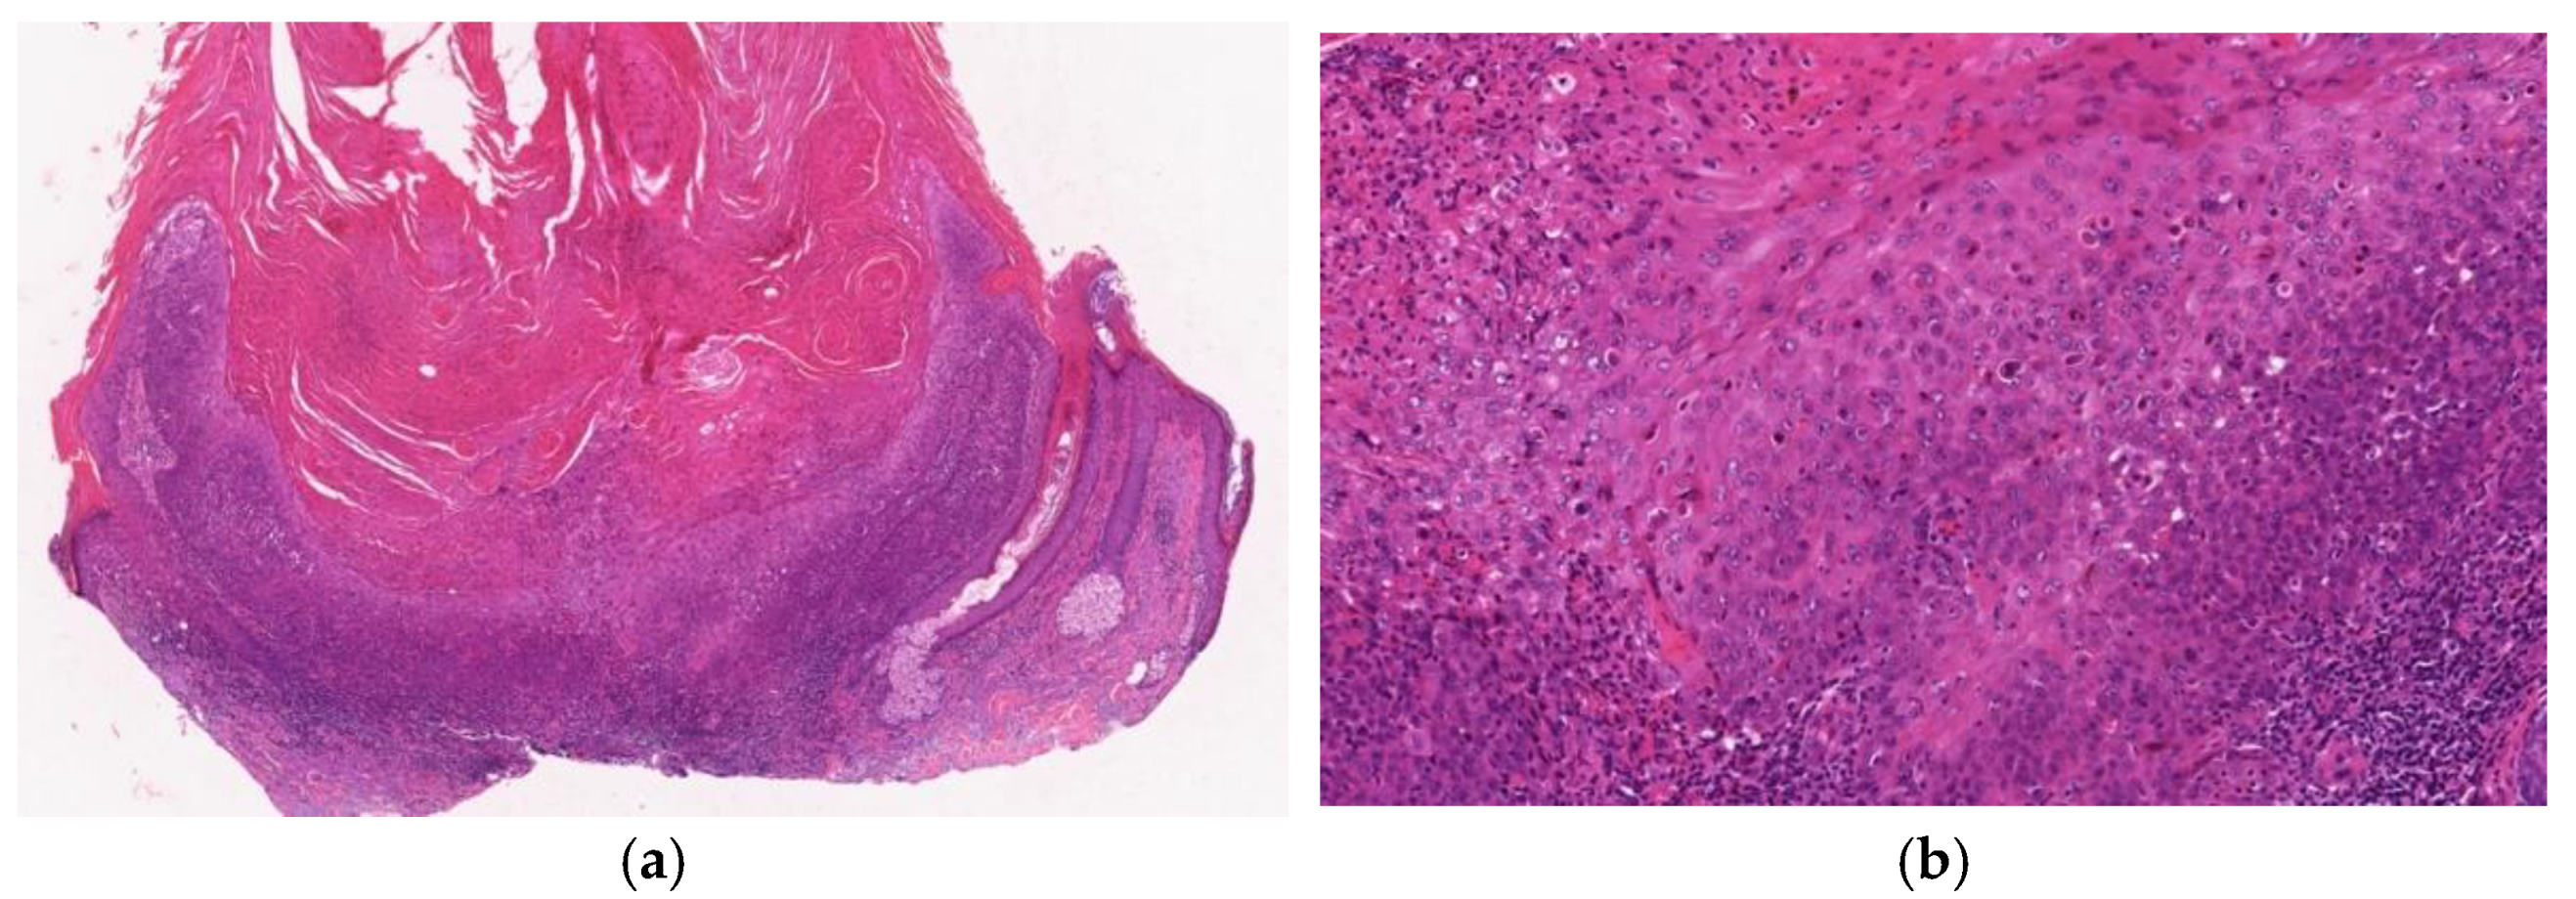

2.2.5. Regressing Stage